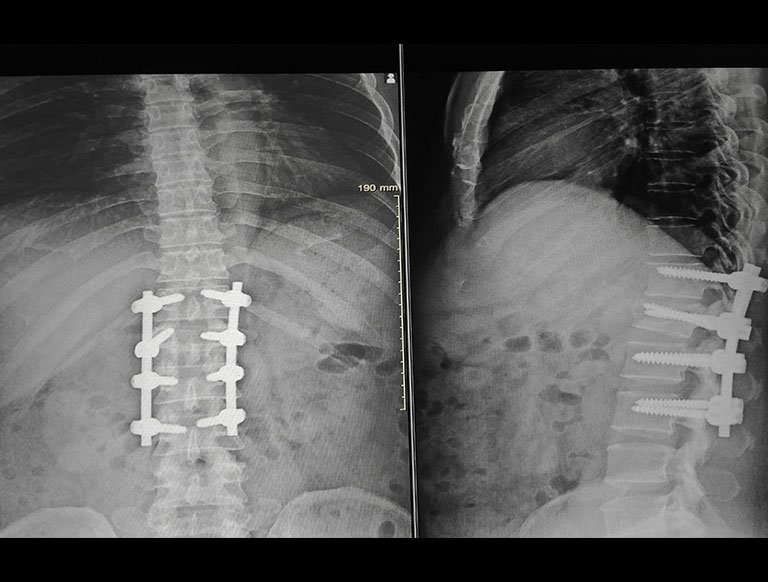

Deformity Correction

Limb deformities can arise due to various causes like birth defect (congenital), neglected or malunited fractures, bone loss. At Summit Orthopaedic Hospital, we are well equipped to treat these conditions. Addressing limb length discrepancy by bone transport by Illizarov ring fixator also available.

Our team is experienced in managing complex cases involving angular deformities, rotational issues, and limb length discrepancies. For patients requiring gradual correction and bone regeneration, specialized procedures like bone transport using the Ilizarov ring fixator system are also available, providing effective and precise outcomes tailored to each individual’s needs.